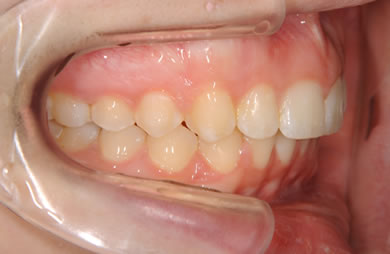

| 性別/年齢 | 女性 / 19歳 | ||||||||||||||||||||||||||||||||

| 治療方針 | 上顎の歯の傾斜を正常に治す事で下顎を正常な位置に推進させ、非抜歯にて治療を行う。また、上下の顎のずれの治療のため、装置にゴムを使用し審美的・機能的に良い咬合を獲得させる。 | ||||||||||||||||||||||||||||||||

| 治療内容 | 唇側矯正(シルバー) | ||||||||||||||||||||||||||||||||

| 総治療費 | 659,300円 | ||||||||||||||||||||||||||||||||

| 治療期間 | 1年9ヶ月 |